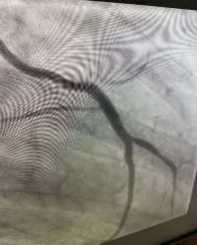

60 year old male known diabetic, hypertensive and dyslipidaemic presented with unstable angina, Coronary angiogram revealed Mid RCA pre crux lesion of 80-90% stenosis and PDA and PLV arising from Mid RCA (Fig 1). It was an angulated bend post bifurcation and hence Fielder FC wire support was taken to easily manipulate the vascular bifurcation (Fig 2) and successful PTCA+ stent to Mid RCA was done with 3x24mm Yukon choice flex stent (Fig 3& 4). TIMI III flow was achieved and post procedure period was uneventful.

FIG 2: Successful manoeuvring of Fielder FC through the bifurcation to PLV